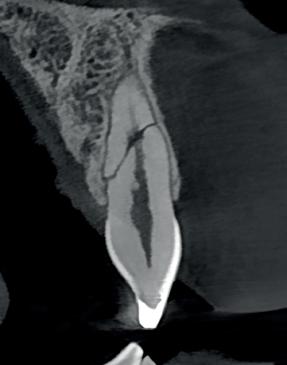

6. Screenshot van de CBCT.

7. Een horizontale fractuur is eigenlijk nooit helemaal recht door het element zoals te zien is op dit screenshot uit een CBCT van een gefractureerd element uit een andere

casus. Met dank aan Patrick Vadasz.